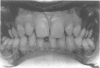

We report two families with the Witkop "tooth and nail syndrome". This term is a misnomer, as the hair was mildly involved in the original case reports and in the families reported here.